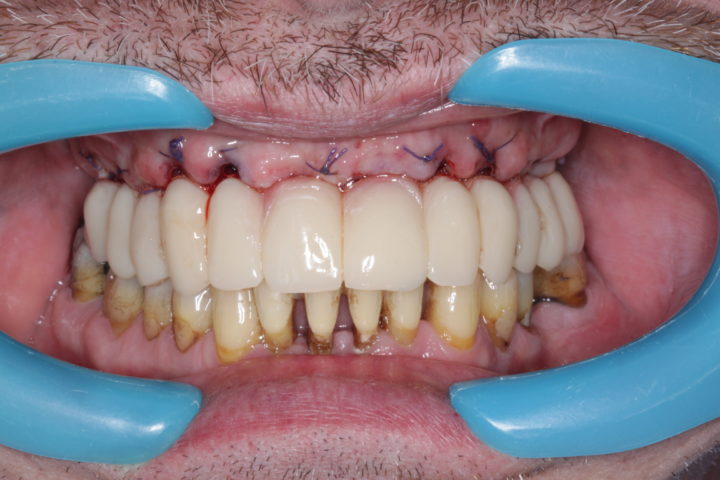

dopo

Caso risolto con Toronto Bridge - Fase iniziale, intermedia e finale